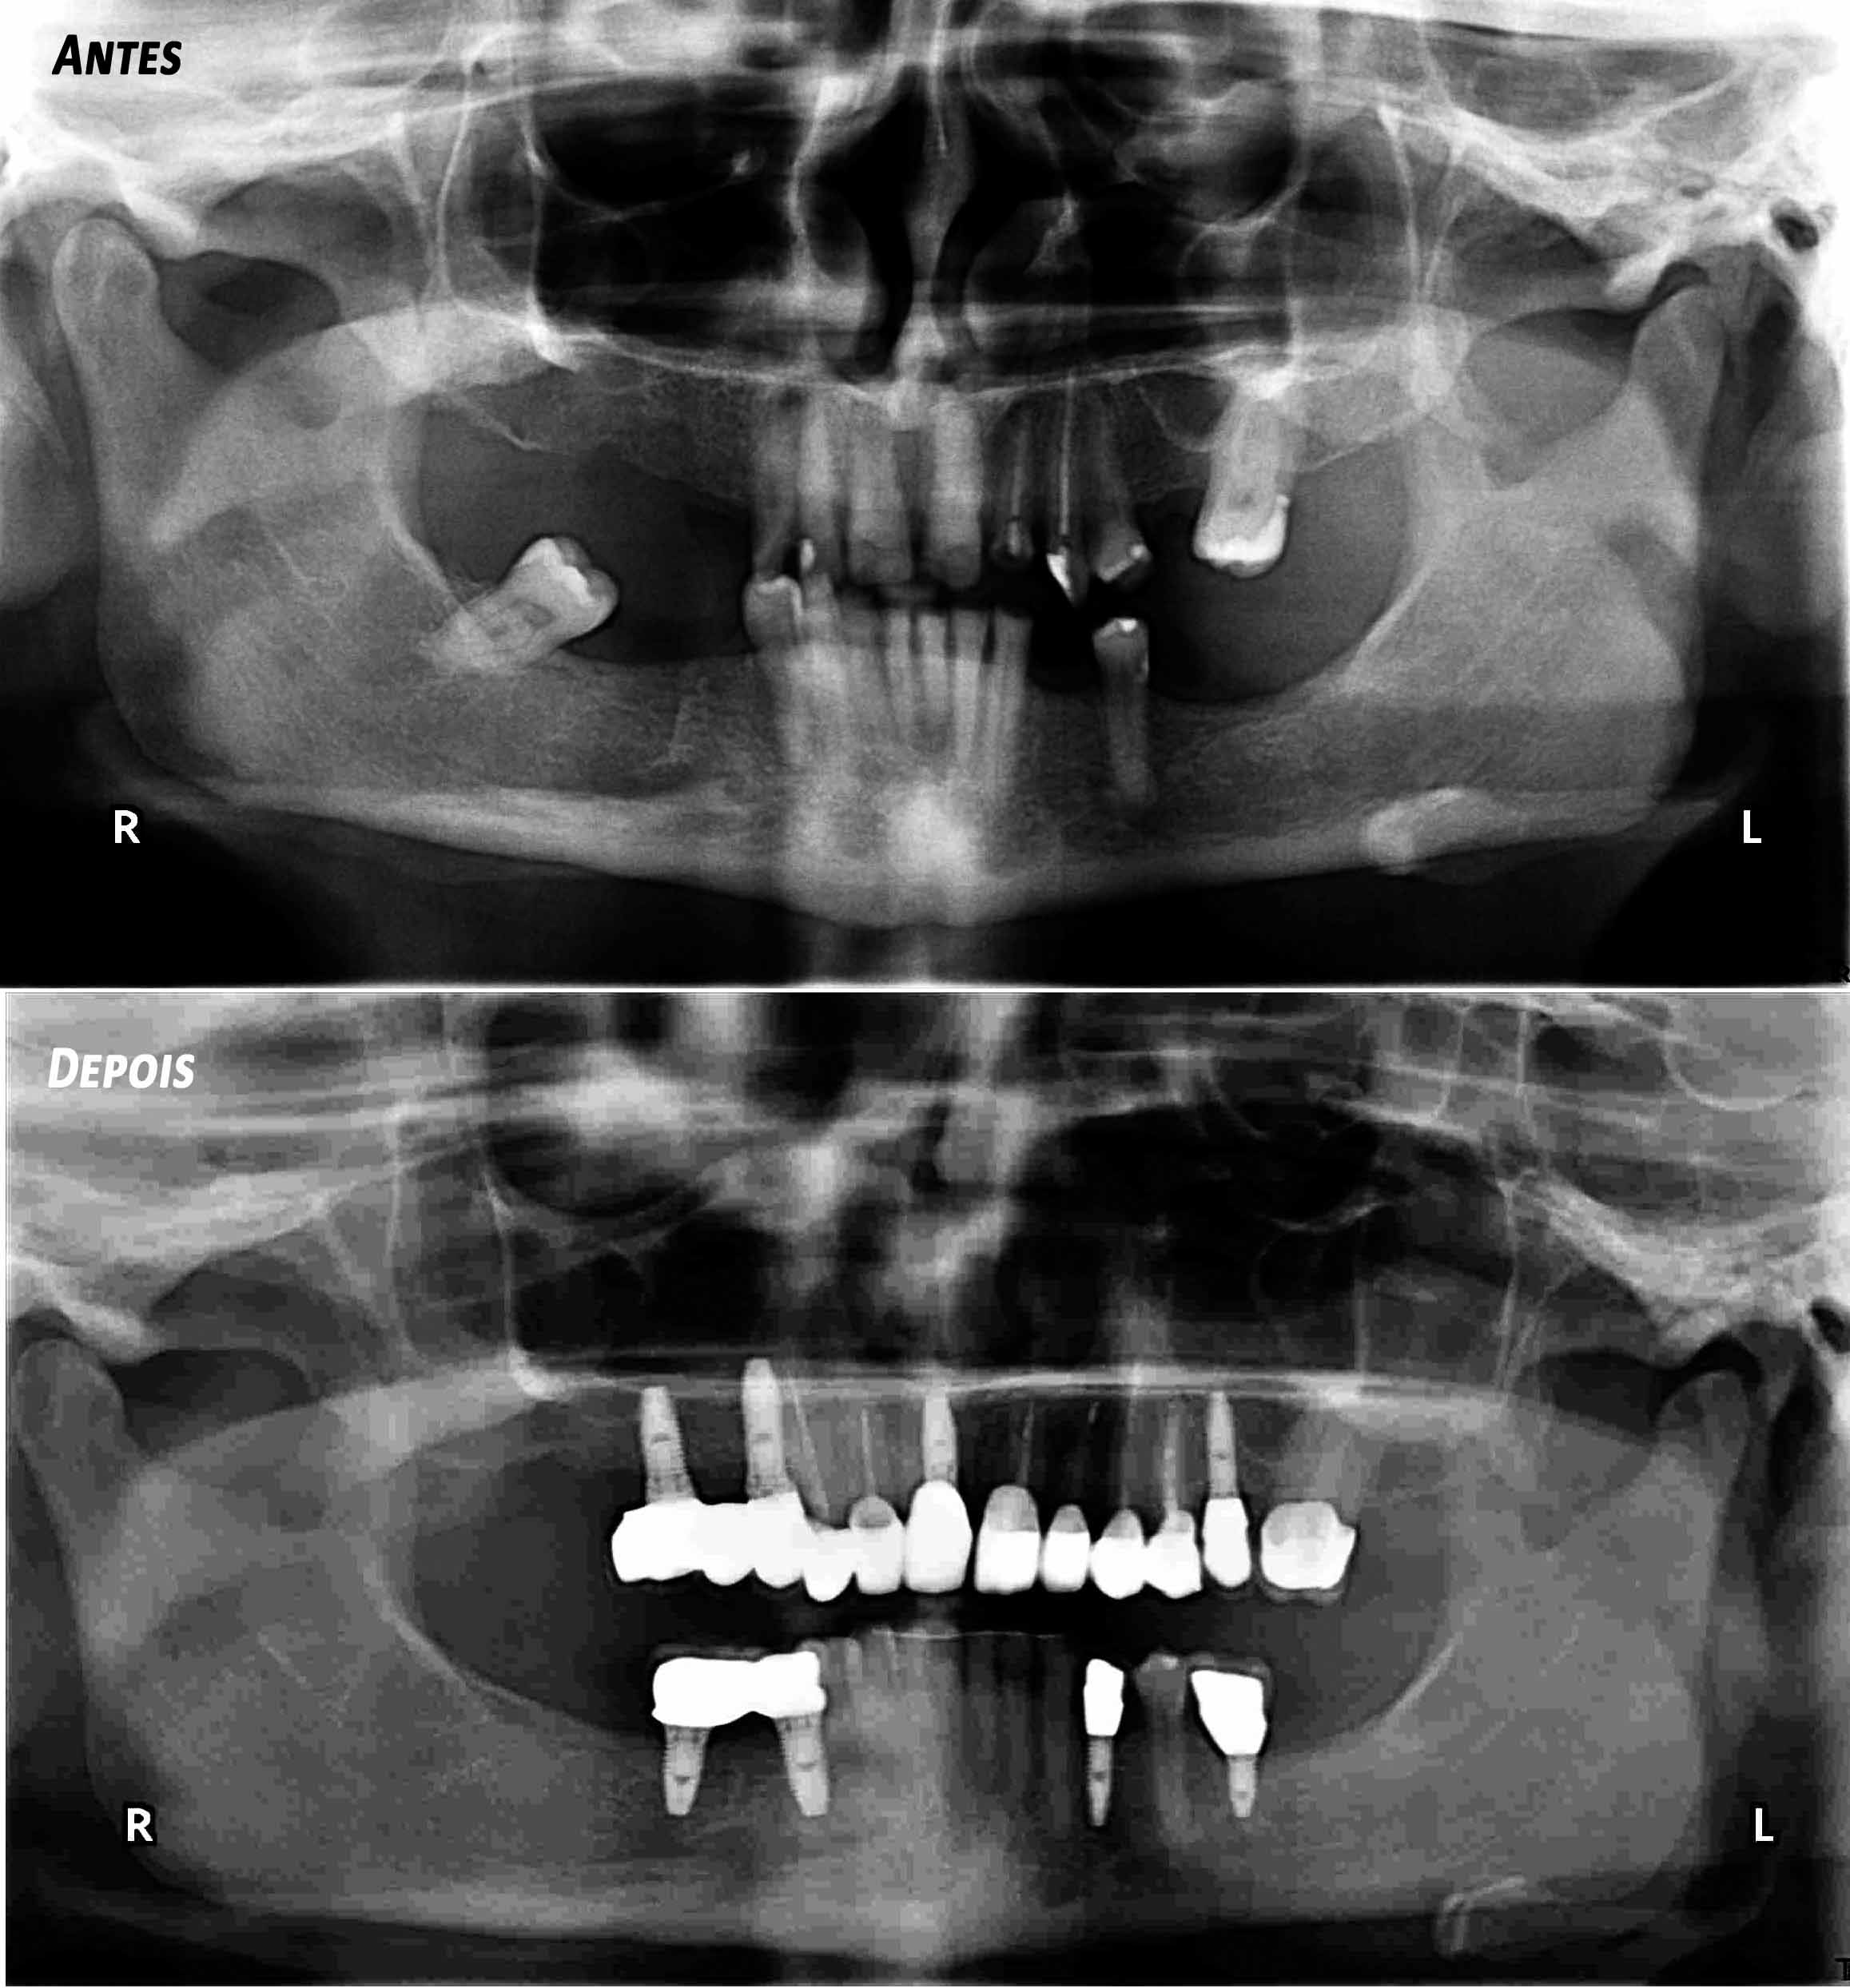

Reabilitação Complexa - Tratamento

Mantiveram-se os dentes naturais remanescentes que tinham bom prognóstico e com Aparelho Ortodôntico fixo foram corrigidas as suas posições.

Posteriormente foi feita cirurgia para colocação de alguns Implantes.

Finalizou-se com colocação de Coroas Cerâmicas.